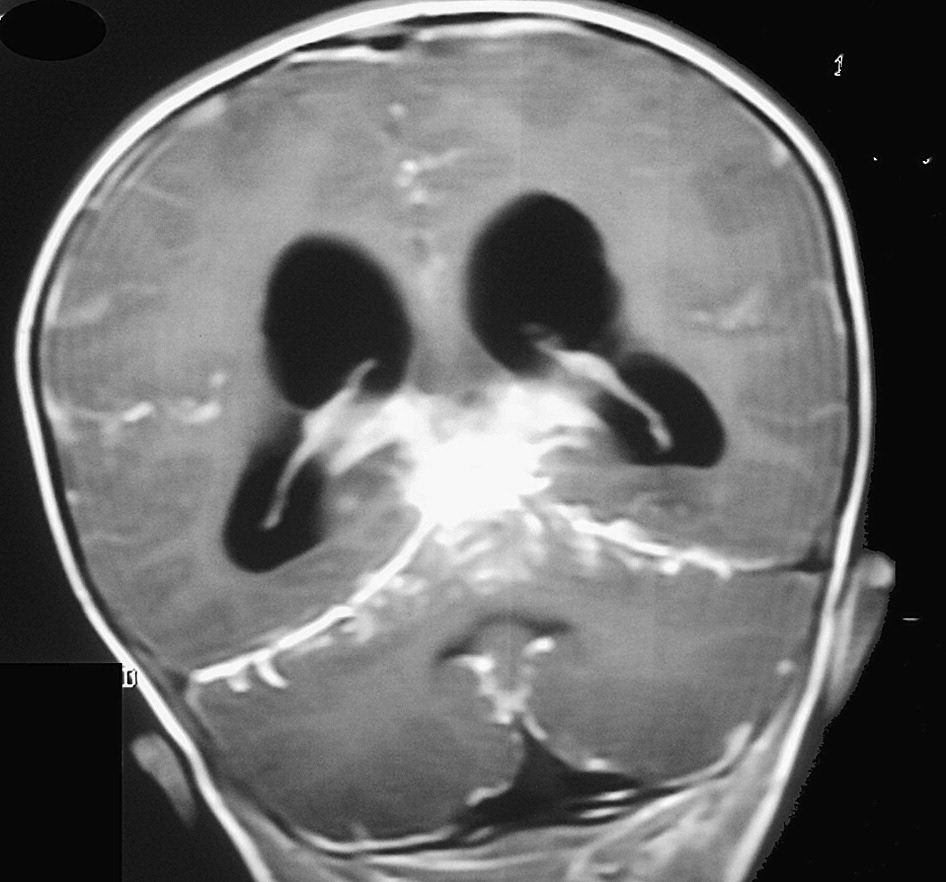

The abnormal thickening of the dura mater of the brain and spinal cord is an inflammatory condition that is quite rare. It is known as pachymeningitis. It depends on the condition, either it can involve the brain or spinal cord as well. There are two types of pachymeningitis.

The etiology of the disease has a diverse classification. Charcot was the first clinical researcher to present the case of pachymeningitis. TB and Syphilis were often linked with pachymeningitis, due to its signs and symptoms. The pathogenesis of this rare condition is still under discovery. It is referred to as an autoimmune disease that can result in aggressive infection. Let’s dig into this article further, to know more about this rare disease.